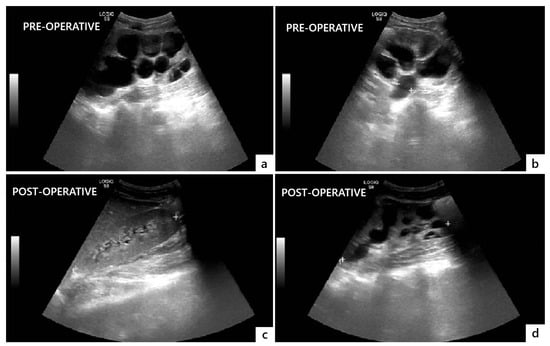

The postoperative course was uneventful, and the patient was discharged on postoperative day 14. He was instructed to regularly void at 3 h intervals and measure the PVR through the suprapubic catheter after each micturition. Postoperative US showed a significant decrease in bilateral hydroureteronephrosis and no significant PVR (Figure 4).

Figure 4. Comparison of preoperative (a,b) and postoperative (c,d) ultrasonographic findings showing resolution of bilateral hydronephrosis and megaureter three months after surgery.